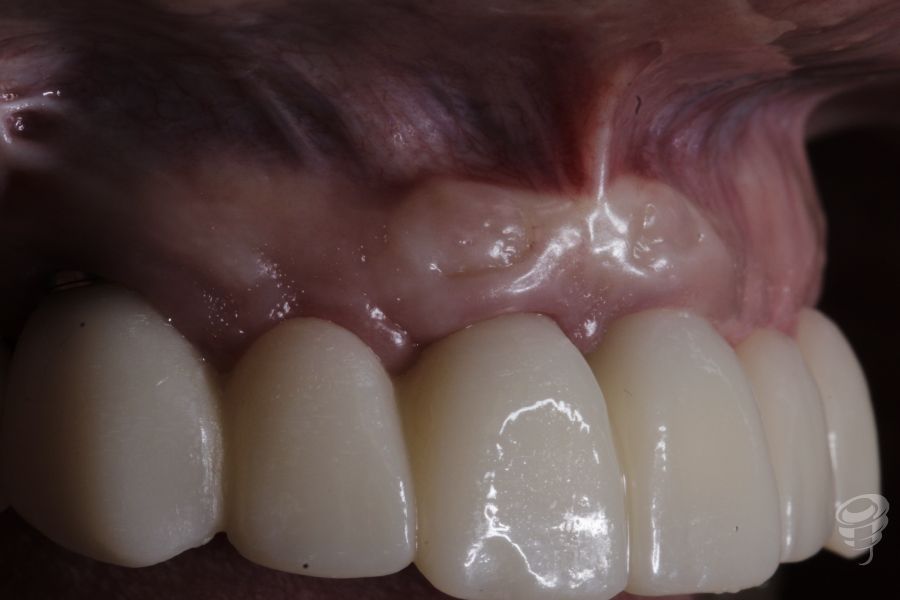

Resultado

Resultado de los perfiles de emergencia, situación estética gingival y protética de un PMMA que será el paso justamente anterior a la prótesis definitiva que se realizará en Zirconio monolítico.